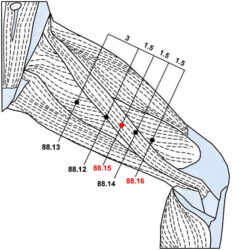

הסבר והדגמה של קריסטל המים 66.13 Shui jing

קריסטל המים 66.13 Shui jing היא נקודה חשובה באקופונקטורה של מאסטר טונג לטיפול בהפרעות גינקולוגיות, בוידאו אני מסביר אודות הנקודה ומדגים את בדרך לאתר ולדיקור.

הסבר והדגמה של קריסטל המים 66.13 Shui jing קרא עוד »